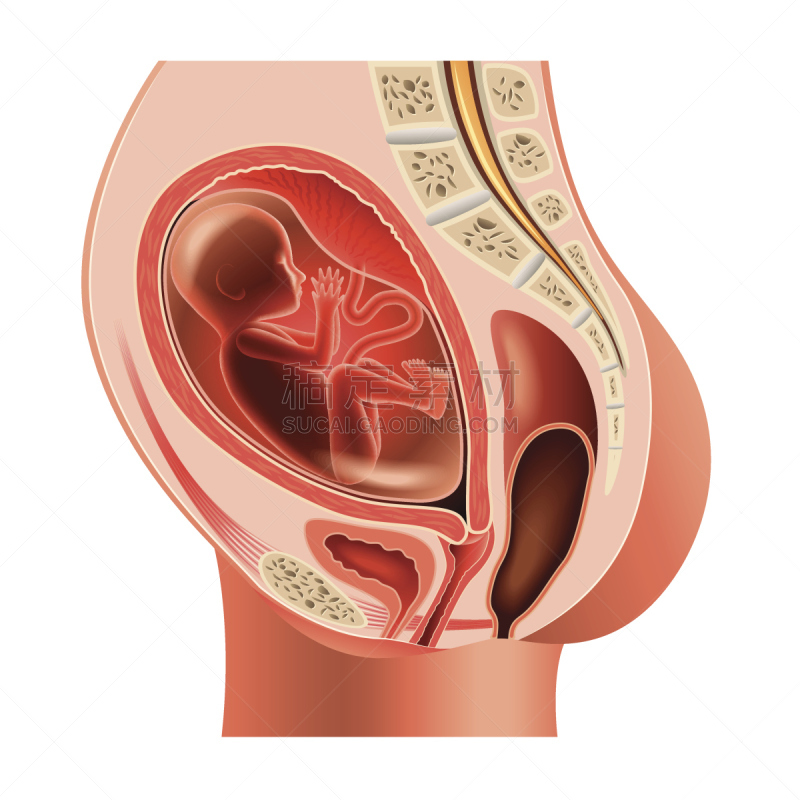

有胚胎的孕妇详情

EPS

怀孕的胎儿详情

EPS